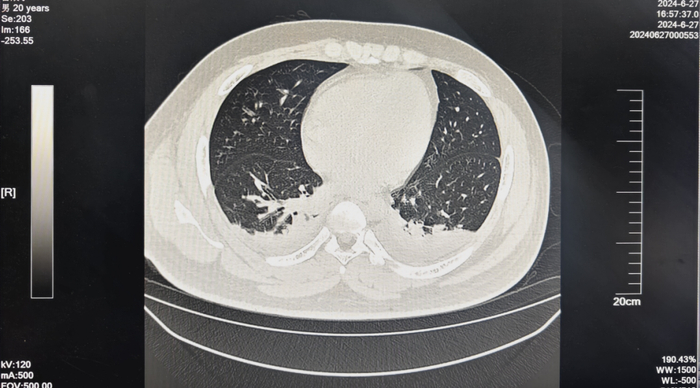

后续患者的恢复情况证实了团队的猜想。从第3周起,患者呼吸趋于平稳,血气分析表明呼吸衰竭情况得到改善,血氧饱和度也逐渐回到了95%以上。到了中毒后的第29天,胸部CT检查显示,患者双肺损伤无再进展,反而是渗出得到了吸收,左侧胸腔积液明显减少。

至此,在50多名医护人员奋战了近1个月后,患者的中毒情况得到了彻底控制,迎来“重生”。

“出院时,他的肝、肾功能均已回归正常状态,只需坚持使用一段时间抗肺纤维化药物,并定期来医院随访,接受康复治疗即可。”杨志前说,“最新的随访结果也显示,他的肺部损伤情况还在持续好转中,我们认为是可以实现‘痊愈’的。”